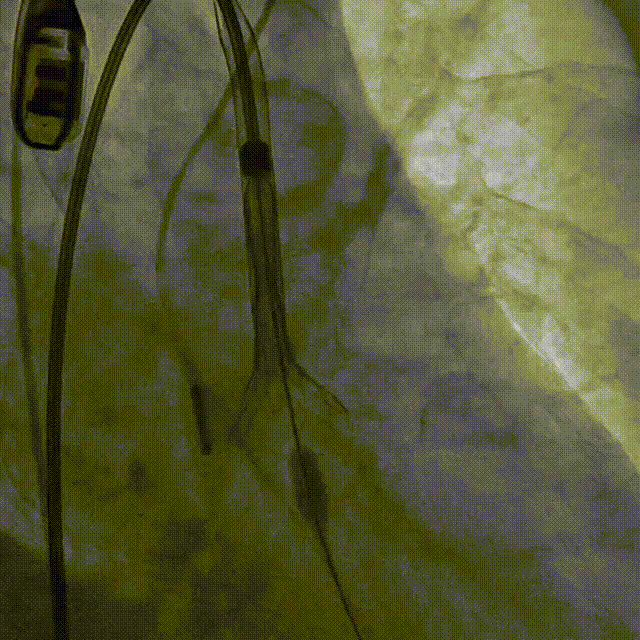

选择22mm球囊进行预扩,结果显示具有明显腰征,无瓣周返流,随即选择TaurusElite26mm瓣膜,凭借其优异的柔顺性,轻松完成过弓。